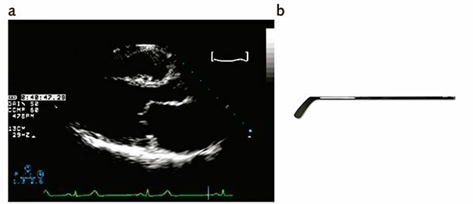

Os aspectos característicos da estenose mitral de origem reumática, à ecocardiografia bidimensional, incluem fusão comissural, espessamento e calcificação das cúspides valvares e do aparelho subvalvar. Observa-se também a típica abertura em “domo” ou “bastão de hóquei” (Figura 1) da cúspide anterior da valva mitral durante a diástole, especialmente nos cortes paraesternal longitudinal e apical. O átrio esquerdo geralmente encontra-se aumentado. No plano transversal, ao se visualizar a valva mitral de frente, é comum identificar o aspecto característico de abertura em “boca de peixe”.

Figura 1 – Janela paraesternal eixo longo ilustrando a cúspide anterior mitral (a) em aspecto de bastão de hóquei (b).